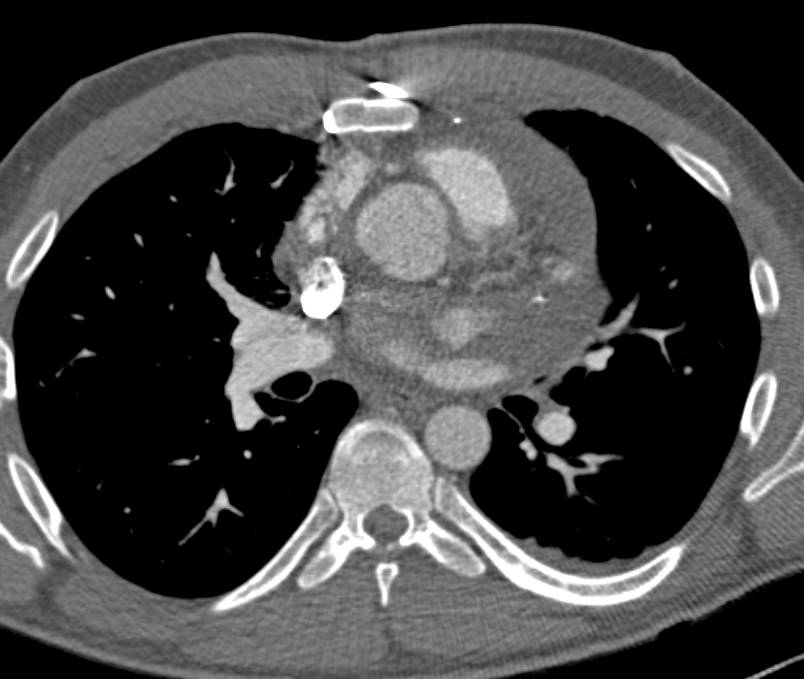

Dilated Aortic Root and Ascending Aorta